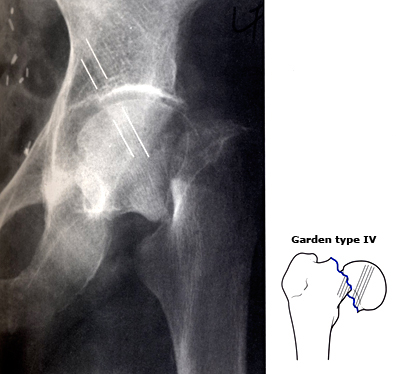

(2)复位打钉子固定

尽管也是做手术也要麻醉,但如下图所示,这种治疗是保留患者自己的骨头,在复位后用3枚钉子加压固定骨折断端,给骨折一个机会,希望它能自己长好。这种方法的优缺点如下:

1)优点:

尽管还要麻醉也是做手术,但是这种手术相对更微创,比关节置换创伤更小,出血更少,花费也更少。

而且因为有三颗钉子的强力加压固定,手术后患者就不疼了,可以在床上翻身坐起并活动髋关节,相较于保守治疗来说,打钉子不仅可以提高骨折愈合概率,加速骨折愈合时间,更能明显改善生活质量,能更好的预防各类并发症。

2)缺点:

尽管创伤小,但毕竟还要*醉药麻**手术,有一定的风险。

而且,在打钉子固定之前,必须把移位的骨折复位好才行,对医生的复位操作水平要求较高。即便复位固定非常好,后期也有很大几率发生骨折不愈合或者股骨头坏死。一旦发生,还需要二次手术,再换人工股骨头。岁数大的人以后还能不能经得起第二次手术,就很难说了。

此外,打钉子后虽然患者在床上活动不疼了,但并不能下地负重,必须在骨折愈合后才能下地。相较于关节置换,这就大大延长了患者恢复正常生活的时间。